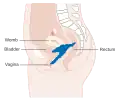

Estadiamento

O câncer do colo do útero é estadiado a partir do sistema estabelecido pela Federação Internacional de Ginecologia e Obstetrícia (FIGO), que se baseia mais no exame clínico do que nos achados cirúrgicos. Apenas os testes a seguir podem ser usados no estadiamento da doença, quando se utiliza o sistema FIGO: palpação, inspeção, colposcopia, curetagem endocervical, histeroscopia, cistoscopia, proctoscopia, urografia intravenosa, conização e radiografia do tórax e do esqueleto.

Estádio 2B

Estádio 2B -

Estádio 3B

Estádio 3B -

Estádio 4A

Estádio 4A -

No estágios iniciais (in situ ou IA) a conização (remover biópsia em forma de cone com bisturi, laser ou LEEP) para diagnóstico já pode remover todo o câncer. O câncer micro-invasor (estágio IA) já indica a remoção de todo o útero (histerectomia total). Remover apenas o cérvix (traquelectomia) permite manter a fertilidade, mas o risco de aborto espontâneo por cérvix incompetente é elevado, esse risco pode ser reduzido com cerclagem. Os estágios IIA e IB indicam remoção dos gânglios linfáticos pélvicos (linfadenectomia), uma cirurgia bastante agressiva e com muito risco de complicações. Quando é maior que 3cm (estágio B) pode-se fazer quimioterapia ou radioterapia antes da cirurgia para reduzir o tamanho do tumor (terapia neoadjuvante). Quando invade vagina, bexiga, cólon, reto, corpo do útero ou peritônio as partes invadidas também podem ser removidos. Em estágios avançados (III ou IV) apenas radioterapia externa e localizada (braquiterapia) e quimioterapia com cisplatina e fluorouracil estão indicados. Imunoterapia também podem ser útil.[45]